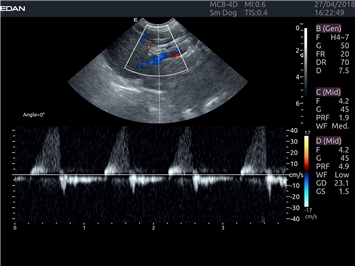

EDAN Acclarix LX4 VET

EDAN Acclarix LX4 VET представляет собой профессиональную ультразвуковую систему, специально разработанную для ветеринарных исследований. Сочетание стабильности, высокой производительности и эффективности делает эту систему идеальным выбором для современной ветеринарной практики.

Постоянно-волновой допплер:

Да

Импульсно-волновой допплер:

Триплексное сканирование: